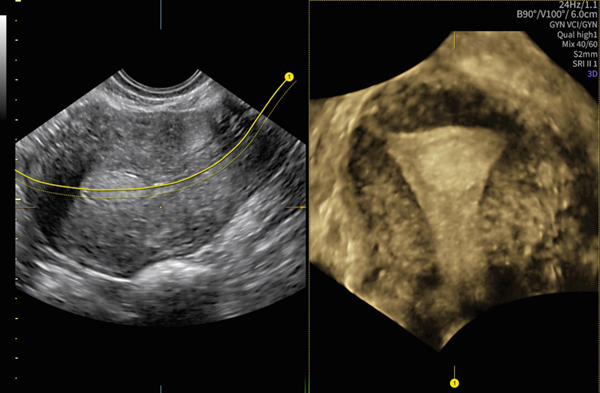

AIを用いて開発したソフトウェアと自動化ツールで,検査時間の短縮とストレス軽減に貢献する。立体表示は正確な診断だけでなく,連携施設との情報共有や患者様への説明支援としても役立つ。

子宮筋腫と子宮,子宮内膜との位置関係を立体表示するFibroid Mappingは,医師同士や患者様とのコミュニケーション円滑化につながる

ラインを引くだけで子宮の断面を自動表示するUterine Traceは,子宮形態の把握に役立つ